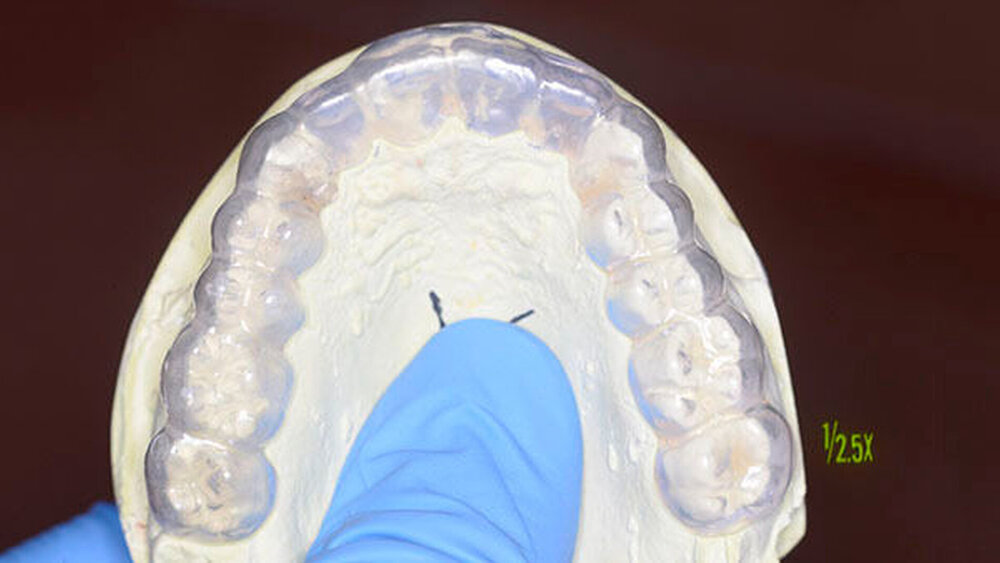

Der Zahn wurde zwei Stunden nach dem Unfall vital replantiert und semipermanent geschient. Die anschließende Abdrucknahme erfolgte unter allergrößter Sorgfalt. Die laborgefertigte Tiefziehschiene schließt die Bereiche der semipermanenten Schiene bis zum Schienenäquator mit ein. Was die Reanastomosierung der Gefäße und Nerven betrifft, ist der Behandler zuversichtlich, reagieren doch auch vital transplantierte Weisheitszähne nach einigen Wochen wieder auf Kältereize.